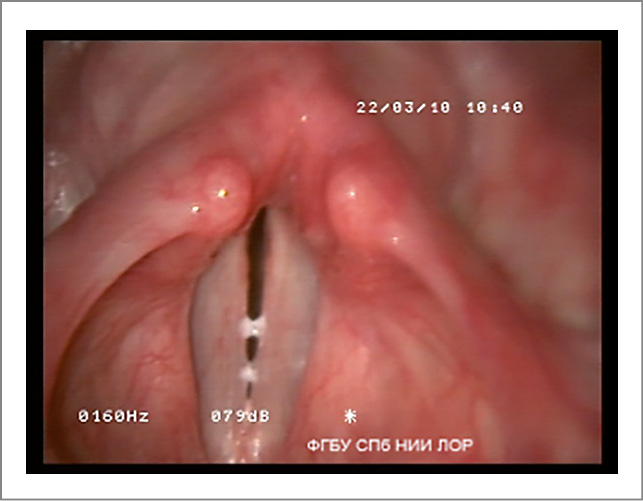

- Симптом «неоднородности» голосовых складок проявляется в том, что lig. vocale и m. vocalis видны изолированными друг от друга образованиями, а не как единое структурное целое (рис. 4).

Рис. 4. Функциональная дисфония по гипотонусному типу (фонация): симптом «неоднородности» голосовых складок.